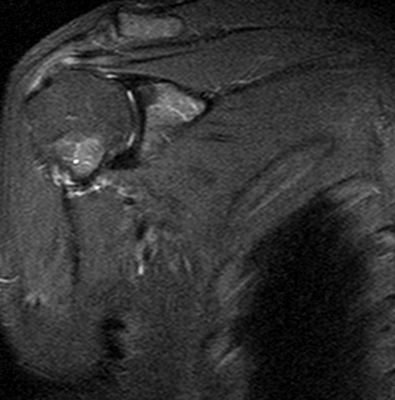

На серии МР-томограмм, взвешенных по Т1 и Т2, а также протонной плотности с использованием режима жироподавления в аксиальной, косой корональной и косой сагиттальной плоскостях определяются структуры правого плечевого сустава. Соотношение в суставе на момент исследования не нарушено. Субакромиальное пространство составляет 6 мм (сужено). Суставная впадина лопатки уплощена, контуры ее ровные, с признаками субкортикального остеосклероза. По краям суставной впадины лопатки имеются небольшие остеофиты. Головка плечевой кости округлой формы не деформирована. Суставной хрящ неоднородной структуры, неравномерно истончен, целостность его не нарушена.

Суставная губа на всем протяжении прослеживается, дегенеративно изменена, без отчетливых признаков нарушения целостности. Средняя суставно-плечевая связка неравномерно утолщена, без нарушения целости, но вокруг отмечается небольшое количество выпота. Сухожилие надостной мышцы на протяжении 24 мм (преимущественно в области мышечного брюшка) утолщено, разволокнено с признаками отека и участками обызвествления, преимущественно изменения отмечаются в передней порции волокон - повреждение сухожилия дегенеративного генеза. Вокруг мышечного брюшка надостной мышцы отмечается небольшой отек межмышечной клетчатки.

Сухожилие подлопаточной мышцы в области прикрепления к малому бугорку плечевой кости утолщено, минимально разволокнено, общая целость его и натяжение сохранены (изменения по типу тендиноза). Сухожилия подостной мышцы в области прикрепления к плечевой кости имеют неоднородную МР- структуру, за счет дегенеративных изменений, целость не нарушена. Сухожилия малой круглой мышцы не изменено. Визуализируется умеренное скопление свободной жидкости в полости плечевого сустава, умеренное в подклювовидной сумке. Сухожилия длинной головки двуглавой мышцы плеча не изменено, вдоль него минимальное количество выпота. Правый акромиально-ключичный сустав дегенеративно изменен: суставные поверхности имеют неровные контуры с наличием краевых костных разрастаний, сами суставные концы с субкортикальным остеосклерозом. Капсула сустава умеренно утолщена.

ЗАКЛЮЧЕНИЕ: МР-картина остеоартроза правого плечевого и акромиально-ключичного сустава I-II ст., признаков импинджмент синдрома с частичным повреждением сухожилия надостной мышцы, умеренно выраженные дегенеративные изменения сухожилия подлопаточной мышцы по типу тендиноза. Синовит. Умеренный теносиновит.